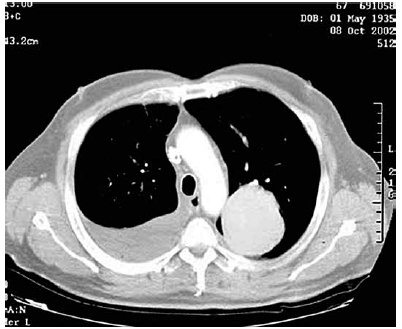

Paciente do sexo masculino, 45 anos, procura ambulatório de clínica médica relatando que há dois meses iniciou quadro de dor em hemitórax direito que piorava com a inspiração profunda. Essa dor diminuiu gradualmente ao mesmo tempo que surgiram episódios de febre baixa (37,9 oC) sempre no final da tarde. Relata emagrecimento de 9 kg nesse período. Tabagista 40 anos/maço. Nega antecedentes mórbidos pessoais ou contato com pessoas doentes. Após exame físico, o médico solicita uma tomografia computadorizada de tórax que está apresentada a seguir.

Enunciado 3014080-1

A dosagem da adenosina desaminase

Analise o caso e responda à questão.

Enunciado 3014079-1

A principal hipótese diagnóstica é: